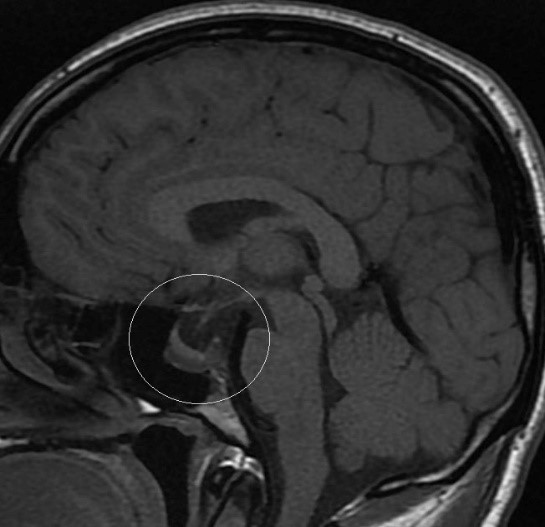

В дальнейшем на фоне постоянного приема вышеуказанной дозировки каберголина сохранялась положительная динамика: поддержание уровня ПРЛ в пределах целевых значений (ПРЛ от 18.01.2017 301.3 мЕд/л (референсный диапазон 60– 510)), уменьшение размеров аденомы (рис.1), что позволило в январе 2017 рекомендовать начать постепенное снижение дозы препарата.К декабрю 2018 г пациент принимал каберголин в дозе 0.5 мг в неделю, уровень ПРЛ находился в пределах нормы – 256 мМЕ/л, по данным МРТ отмечалось дальнейшее уменьшение размеров пролактиномы: инфра –, параселлярное распространение, размеры 12х20х18 мм, снижение ретроселлярного распространения (рис.2). При эхокардиографическом исследовании структурных и функциональных нарушений не выявлено. В настоящее время наблюдение за пациентом продолжается.

Рис. 2. Изменение размеров и распространения образования гипофиза через 5 лет терапии каберголином

2. Рис. 2. Изменение размеров и распространения образования гипофиза через 5 лет терапии каберголином

3. Рис. 2. Изменение размеров и распространения образования гипофиза через 5 лет терапии каберголином.(декабрь18)(декабрь13)